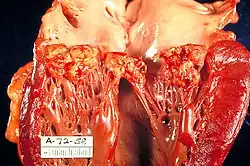

| A mitral valve vegetation caused by bacterial endocarditis | |